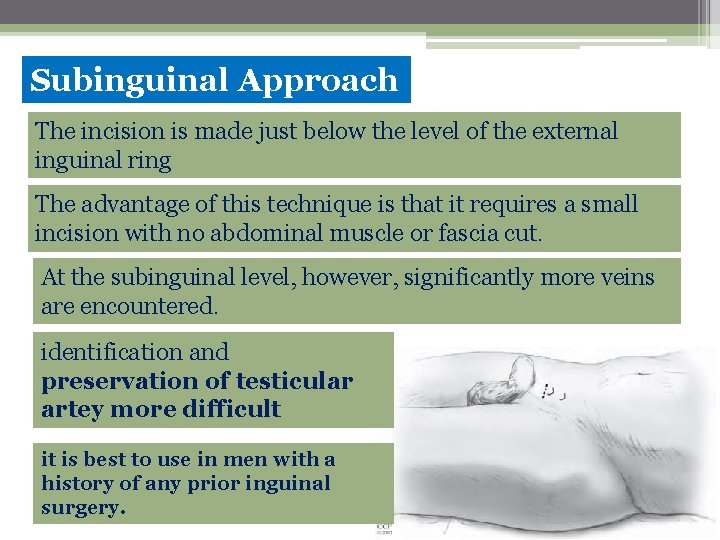

Subinguinal Approach The incision is made just below the level of the external inguinal ring The advantage of this technique is that it requires a small incision with no abdominal muscle or fascia cut. At the subinguinal level, however, significantly more veins are encountered. identification and preservation of testicular artey more difficult it is best to use in men with a history of any prior inguinal surgery.